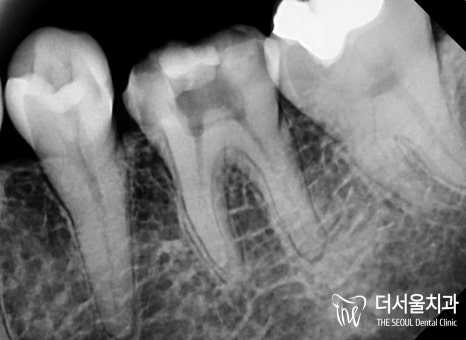

왼쪽은 이차우식으로 인해 염증이 생겨

불편함이 생긴 것으로 확인되었습니다.

【 개선 후 모습 】

순차적으로 진료를 진행하여

감염된 곳을 깨끗하게 청소하고

밀폐, 소독, 충전을 진행했습니다.